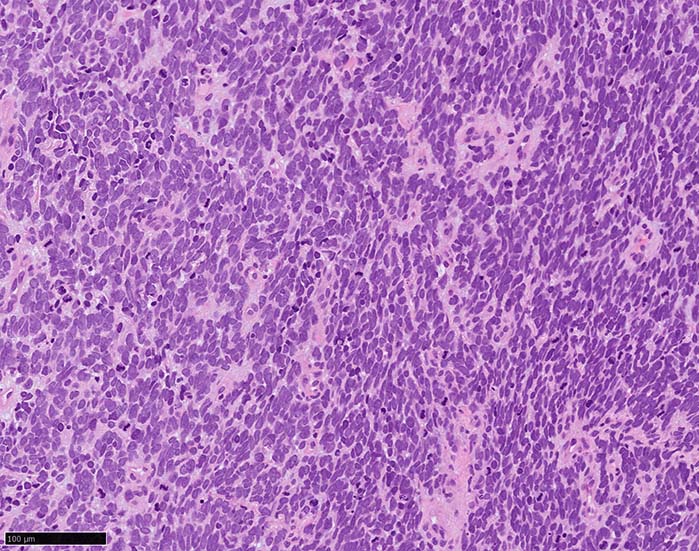

皮膚原発性Merkel細胞癌は 通常真皮を病変首座に増殖し, しばしば脂肪織まで浸潤する.

表皮とは連続性がなくGrenz zoneがみられるのが特徴であるが, 病理所見は多様であり, ときに表皮向性を示す症例やpagetoid patternを呈する症例もある.

典型的な腫瘍細胞は円形, 卵円形の比較的均一な形態で「salt-and-pepper」と称される微細顆粒状クロマチンを有する小型円形核をもつ. MCPyV陽性例が均一な小型円形核を呈する傾向があり, 陰性例では, 核多形性が目立つととする報告がある.

trabecular type, intermediate type, samll cell typeの3パターンの組織型に分類されているがしばしば混在している.

- small cell typeは濃いクロマチン, 多形性を示す核をもつN/C比大の小型腫瘍細胞がびまん性に増殖する.

- intermediate typeではtrabecular, samll cell typeの中間の腫瘍細胞サイズを示す. 組織型としてはもっとも多い.

血管を間質にしてround cellsが索状に増殖する所見. rossett様配列がある. CK20は特徴的な dot-like patternを示す. クリックで大きな画像が見られます.